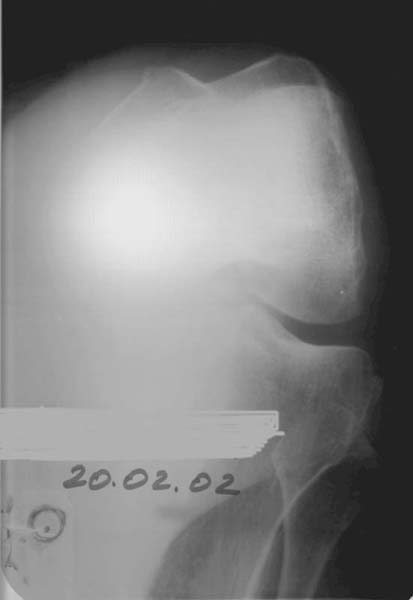

At the present time a post traumatic defect of lateral femoral condyle is observed. On the X-rays of left knee, a lateral femoral condyle defect is observed up to the 1/3 of the joint surface. Clinical examination of left knee joint revealed moderate atrophy of the muscles of left femur and shin, moderate pain with palpation of the lateral joint line, pathological deviation of the shin to the outside up to 20 degrees at doing the clinical tests, accompanied by the appearance of moderate pain, motions in the knee joint are slightly restricted.